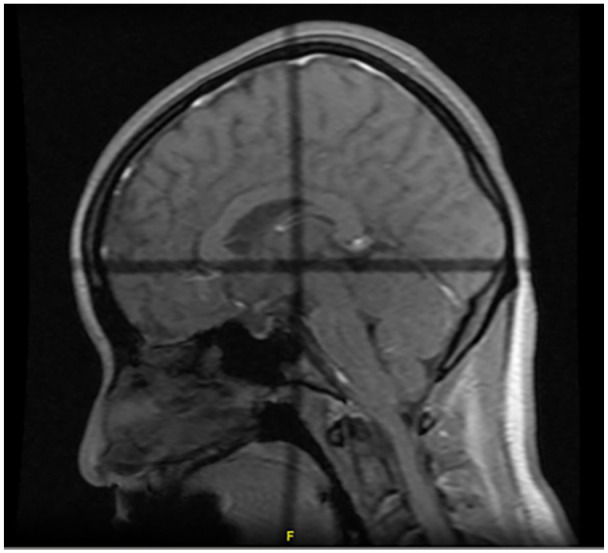

Cryptococcal meningitis is mainly seen in immunocompromised patients, but in recent years, there has been an increase in cases involving patients with no known immunodeficiencies. These patients have symptomatic presentations that range from indolent and mild to typical and severe. We present a case of cryptococcal meningitis in an immunocompetent young patient with a chronic headache. The patient underwent imaging which showed diffuse leptomeningeal enhancement and a lumbar puncture which confirmed Cryptococcus neoformans. She underwent guideline-based treatment for cryptococcal meningitis and improved clinically. Cryptococcal meningitis should be considered in immunocompetent patients who present with typical signs of symptoms of meningitis, particularly chronic headaches and altered mental status.